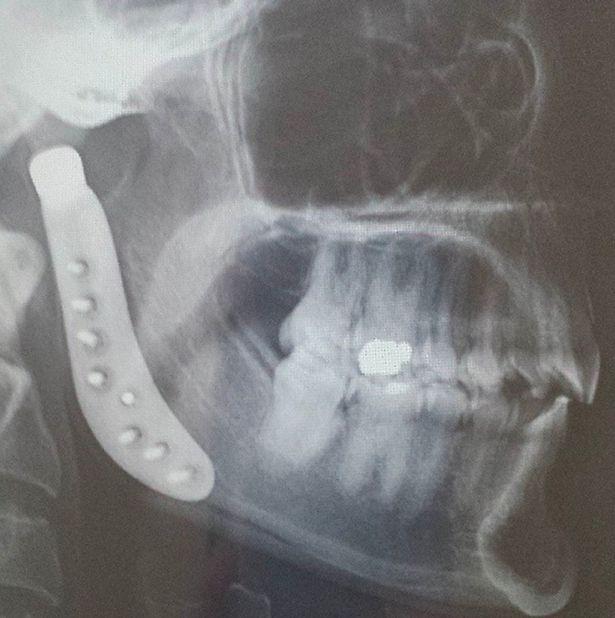

Ngay sau đó, cô quyết định đến nha sĩ kiểm tra. Bác sĩ chẩn đoán Tamara bị lệch đĩa đệm khớp thái dương hàm bên phải. Có vẻ như chiếc đĩa đệm này đã lệch từ rất lâu rồi, và giờ nó biến thành viêm thoái hóa khớp. Cô đã trải qua một thủ thuật để sửa hàm nhưng mọi chuyện còn tồi tệ hơn.

Sau đó, bạn bè cô đã lập một tài khoản vận động từ thiện có tên là GoFundMe để kêu gọi sự trợ giúp của mọi người. Năm 2013, Tamara trải qua cuộc phẫu thuật kéo dài 5 giờ đồng hồ để thay thế hàm. Nó tiêu tốn 17.000 USD (khoảng 400 triệu đồng) . Tuy nhiên, chỉ vài tháng sau đó, cô còn cảm thấy đau đớn hơn và xuất hiện nhiều biến chứng lạ trên da.

Một bác sĩ da liễu nói với Tamara rằng cô bị dị ứng với niken và coban - hai chất có trong khớp nối giả thay thế ở hàm của cô sau phẫu thuật. "Mặt tôi sưng tấy trông rất đáng sợ. Cuộc phẫu thuật này phức tạp hơn, tôi sẽ phải đóng hàm và không được cử động phần hàm ít nhất 6 tuần... Tôi lo rằng sẽ không có ai chăm sóc con gái cho tôi".

"Năm 2016, những cơn đau ngày càng kinh khủng hơn và tôi biết mình phải thay thế hàm lần nữa", Tamara chia sẻ. May mắn lần này, khớp hàm giả bằng titanium không khiến cô dị ứng; tuy nhiên, bà mẹ này đang phải đối mặt với nguy cơ sức khỏe khác do ảnh hưởng lâu dài của các chất có trong khớp hàm giả khiến cô bị dị ứng trước đó.